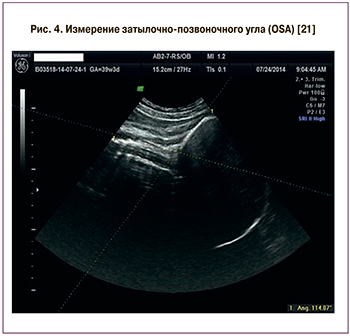

Современные исследования предполагают использование УЗИ для прогнозирования успешных вагинальных родов или большой вероятности КС уже в первом периоде [18–20]. В работе T.M. Eggebø et al. [20] было установлено, что передний вид затылочного предлежания, угол прогрессии (AoP) больше 110° и расстояние между головкой плода и промежностью (HPD) меньше 40 мм являются предикторами успешных вагинальных родов при длительном первом периоде. В исследовании T. Ghi et al. [21] был описан новый УЗ-параметр – затылочно-позвоночный угол (OSA), угол между затылком и шейным отделом позвоночника плода при переднем виде затылочного предлежания, измеряемый трансабдоминально при открытии шейки матки 3-6 см (рис. 4).

Было замечено, что при затылочно-позвоночном угле менее 125° роды чаще заканчиваются оперативно: вакуум-экстракцией плода и операцией КС [21]. Кроме того, в группе с затылочно-позвоночным углом менее 126° повышен риск разрывов влагалища (22,4 и 6,3%) и промежности (10,4 и 5,1%) по сравнению с группой, в которой затылочно-позвоночный угол больше 126° [19]. Следует отметить, что окружность головки плода больше 350 мм в 2,5 раза увеличивает риск любых оперативных родов и в 2 раза – КС из-за дистоции [22]. Возможность прогнозирования исхода родов при использовании ультразвуковой оценки ряда размеров плода и параметров пространственных взаимоотношений головки и таза матери в первом периоде родов представлена в таблице 1.